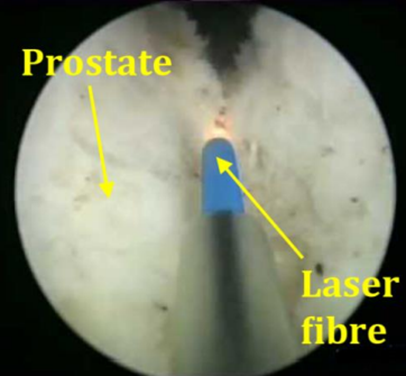

Intervenția care vă este propusă se numește enuclearea endoscopică a prostatei. Ea este practicată cu ajutorul unei fibre si a unui laser. Acest tratament este realizat fără nici o incizie, ci doar pe căile naturale urinare (transuretral). Intervenția constă în lărgirea canalului uretrei prin rezecția adenomului ce se găsește în centrul prostatei. Zona periferică a prostatei este prezervată.

Această intervenție este realizată sub anestezie generală sau rahidiană. Medicul urolog introduce la nivelul canalului uretral un aparat numit endoscop care îi permite vizualizarea uretrei si reperarea prostatei. Cu ajutorul unei fibre laser medicul urolog poate introduce endoscopul între adenomul de prostată și capsula prostatei. Astfel, făcând tot turul adenomului de prostată, medicul urolog detașează adenomul de capsula prostatei și împinge adenomul în vezica urinară. Adenomul complet liber este extras cu ajutorul unui instrument ce se numește morcelator, care permite morcelarea (tăierea) adenomului de prostată în mici fragmente ce pot fi extrase prin aspirare prin interiorul endoscopului.